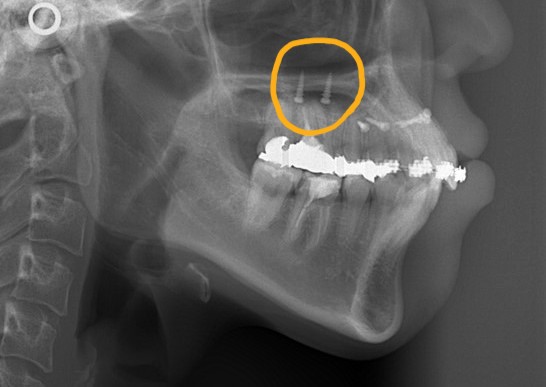

アンカースクリュー:

上顎に計6本(前歯に2本、奥歯に2本、口蓋に2本)使用

ステップが進み歯列が揃ったところで、ガミースマイル改善のために、上顎にアンカースクリューを植立することにしました。

部位は、上顎の口蓋の真ん中、臼歯部(左右側とも)と前歯部の頬側、になります。

アンカースクリューを用いて矯正力を加えることで、上顎歯列全体を圧下させて、ガミースマイルの改善を図ります。